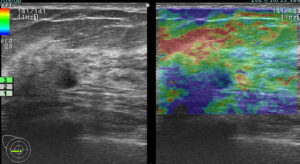

上に挙げた4つのエラストグラフィー

これが何を物語っているか?

エラストグラフィーは何か所見があった際に「これは怪しい!」と思わない限り追加で行わないものです。

これを実は4回も(昨年)行っていたのです。

つまり、(昨年も)その技師は「明らかに癌を疑っていた。」

この4枚のエラストグラフィーは技師の「これは怪しい所見です!是非要精査にしてください!」という心の叫びと言えるんだね!

まさに、その通り!

ただ、悲しいかな。技師さんのその「必死な思い」は、検診画像評価を行う医師には伝わらなかった。

結局、検診結果を出すのは(その画像を見て判断する)医師なのです!

正に診断の問題点1「画像評価」の過ちがここにありました。